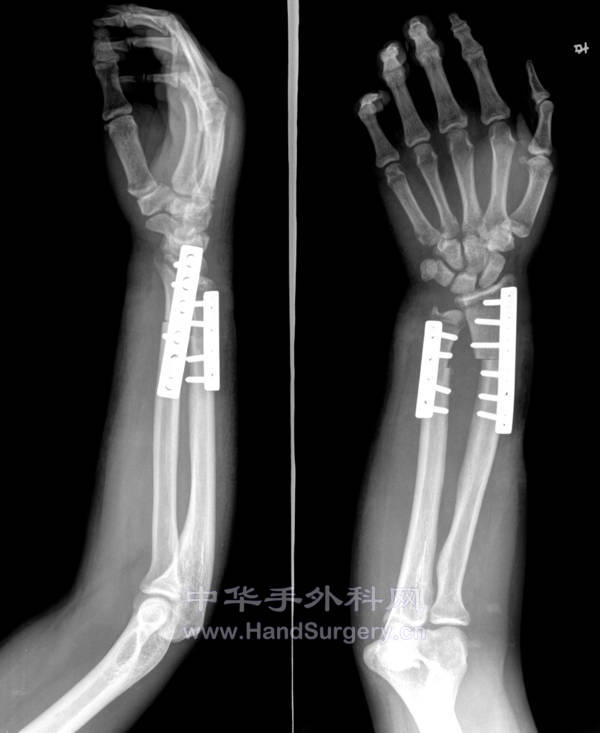

术后一个半月

术后一个半月.jpg

骨折是钢板固定的,局部皮瓣加植皮一期完成手术,其它待二期重建。